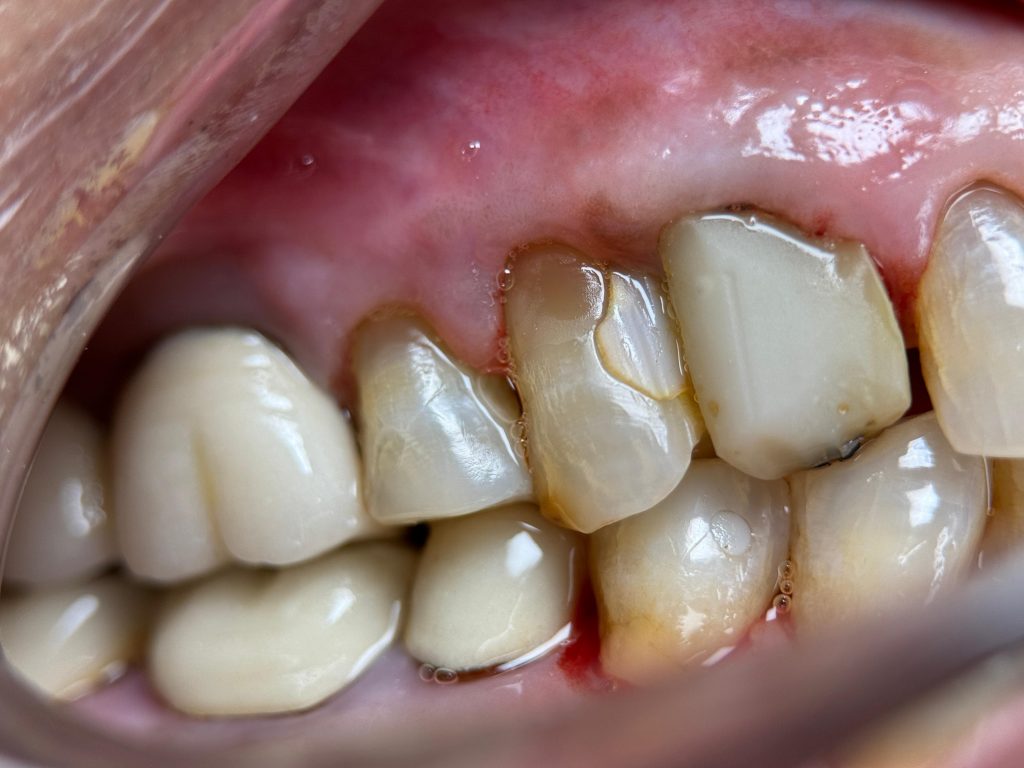

A middle-aged patient presented with the complaint of food impaction and sensitivity in the upper left posterior quadrant. Clinical examination revealed:

- Defective old composite and amalgam restorations

- Leaking margins and plaque retention zones

- Discolouration and structural weakness

- Localised tenderness on biting

- Short clinical crowns

DEEP MARGIN ELEVATION (DME)

Subgingival distal margins were identified in UL6 and UL7. To avoid crown lengthening surgery and preserve periodontal architecture, Deep Margin Elevation (DME) was performed:

- Rubber dam inversion achieved for moisture control

- Sectional matrix band adapted

- Adhesive protocol followed

- SDR bulk flowable composite layered to elevate the margin supragingivally

- This allowed controlled impression, better crown fit, and long-term periodontal compatibility